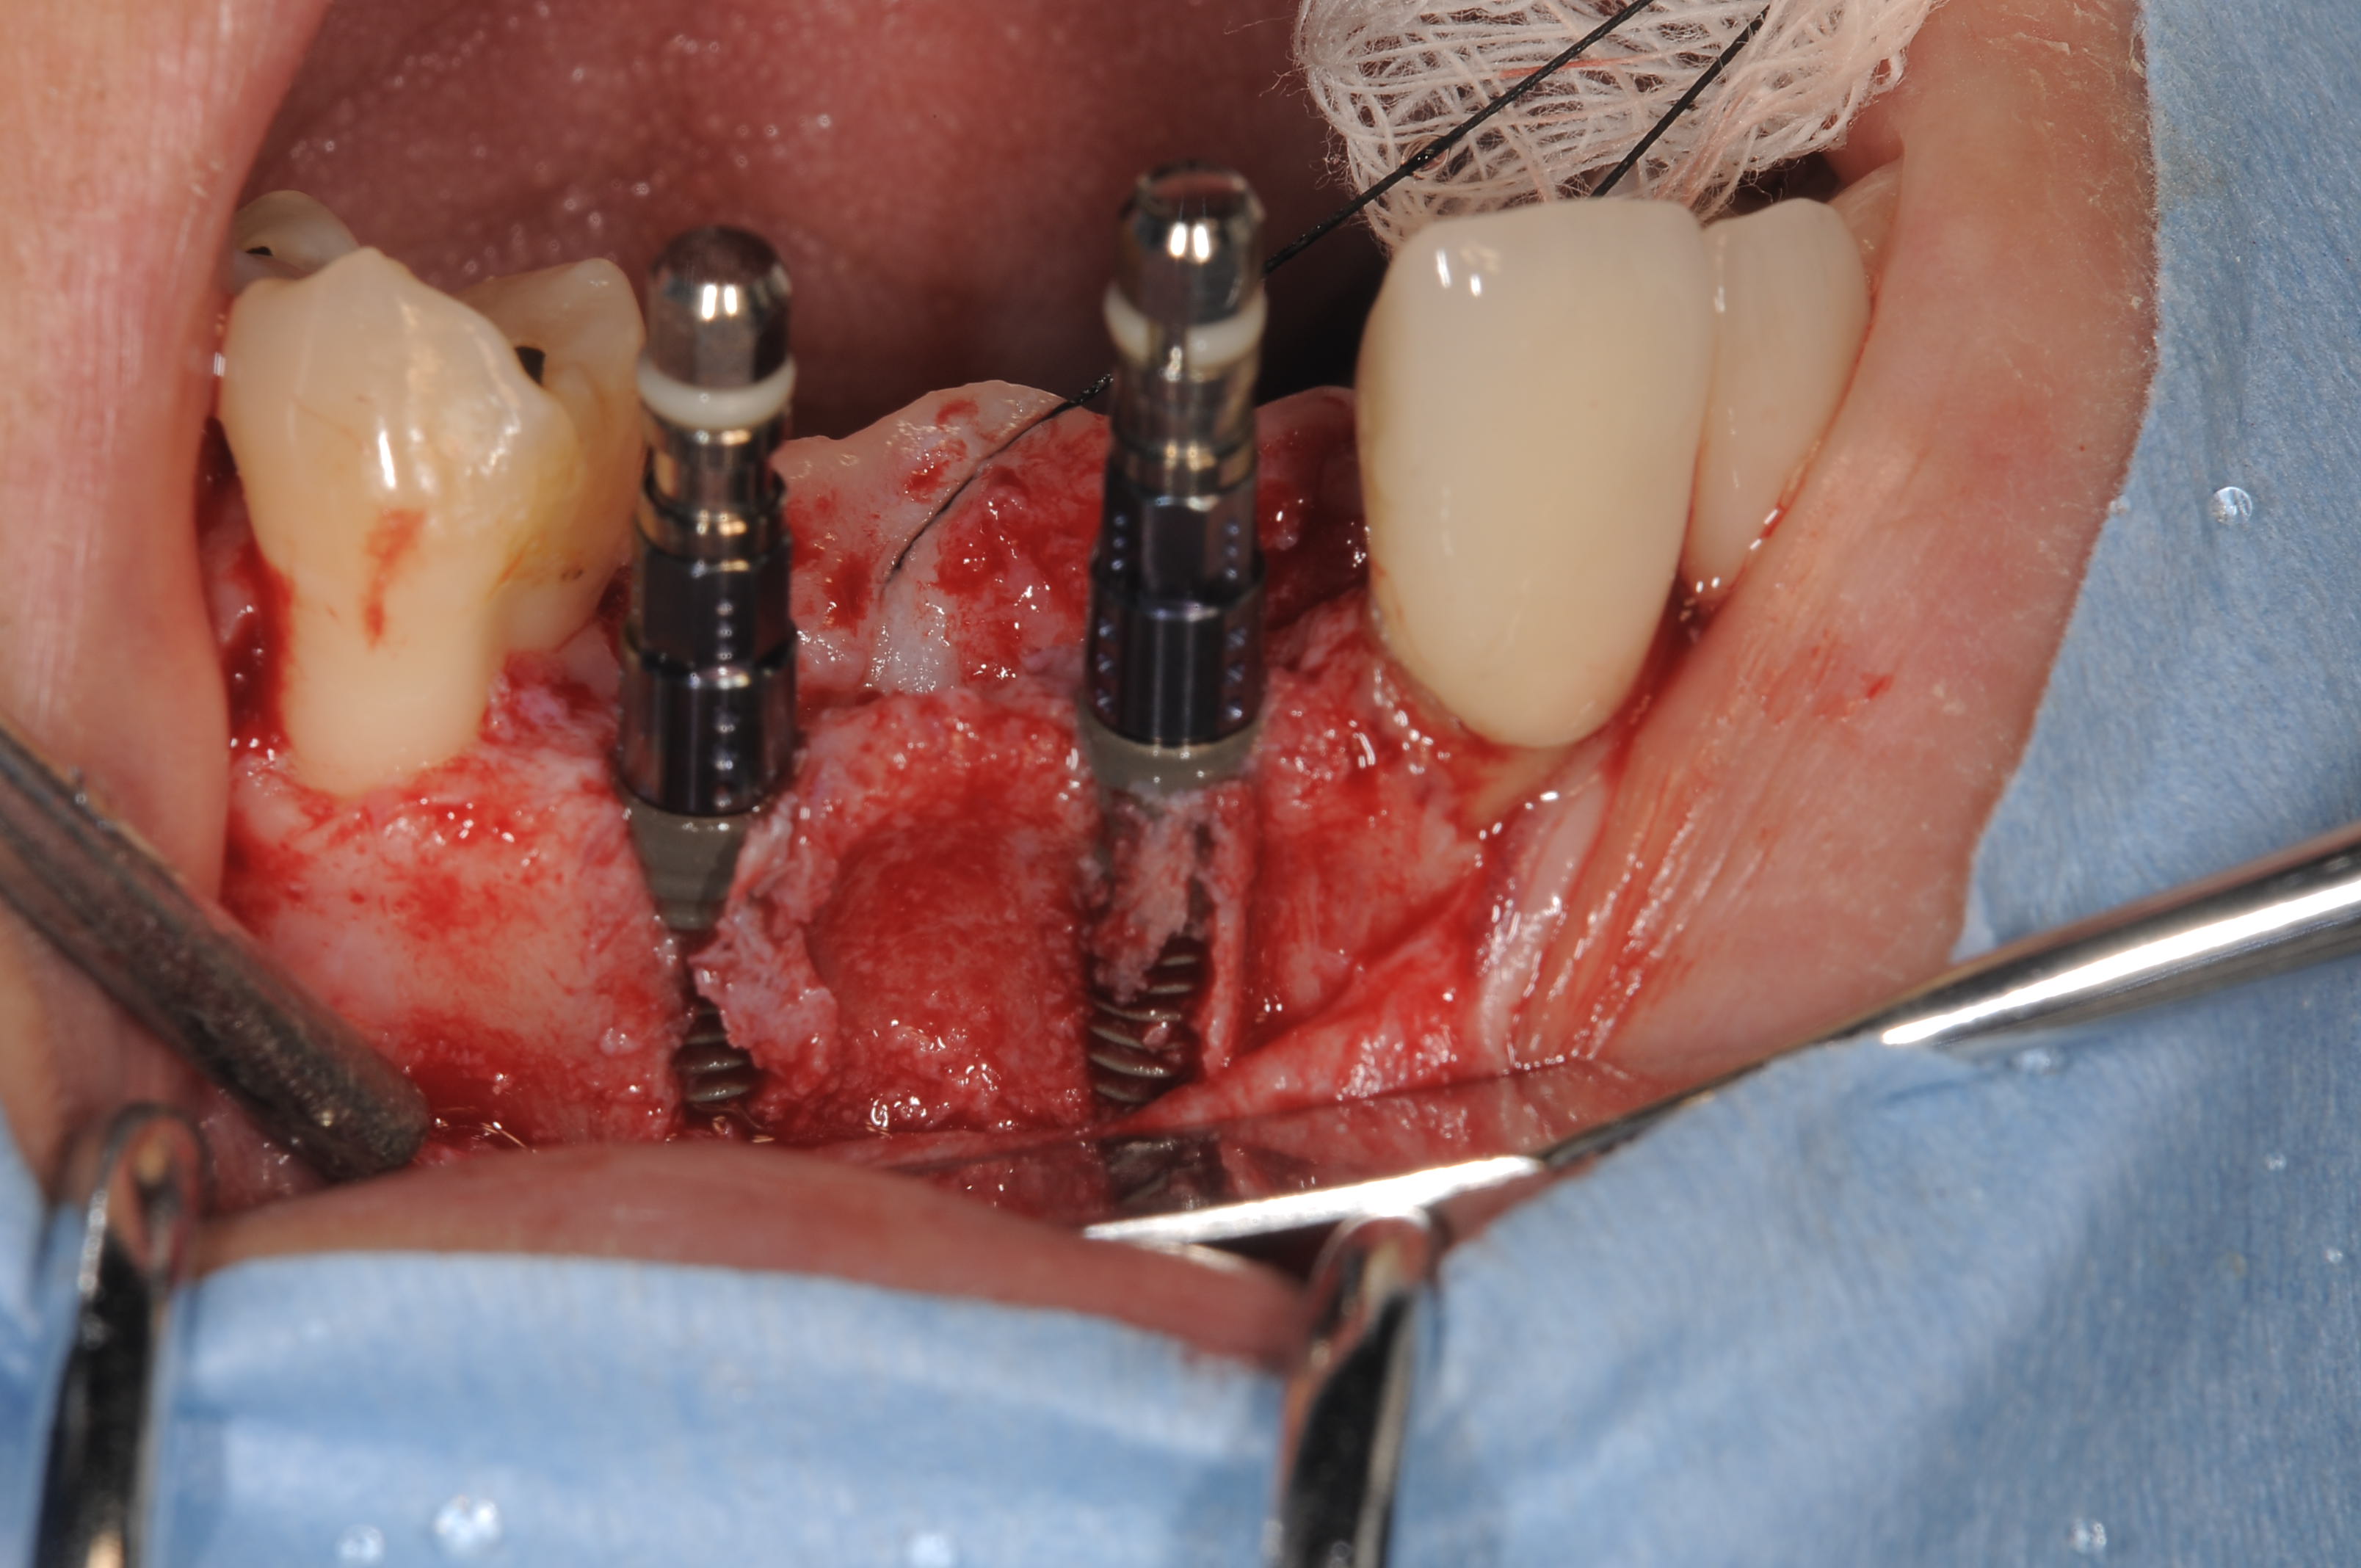

埋入後には頬側に骨の裂開が見られます。

Bio-ossとBio-guideの黄金コンビで埋入と同時法のGBR(Guided Gone Regeneration)です。